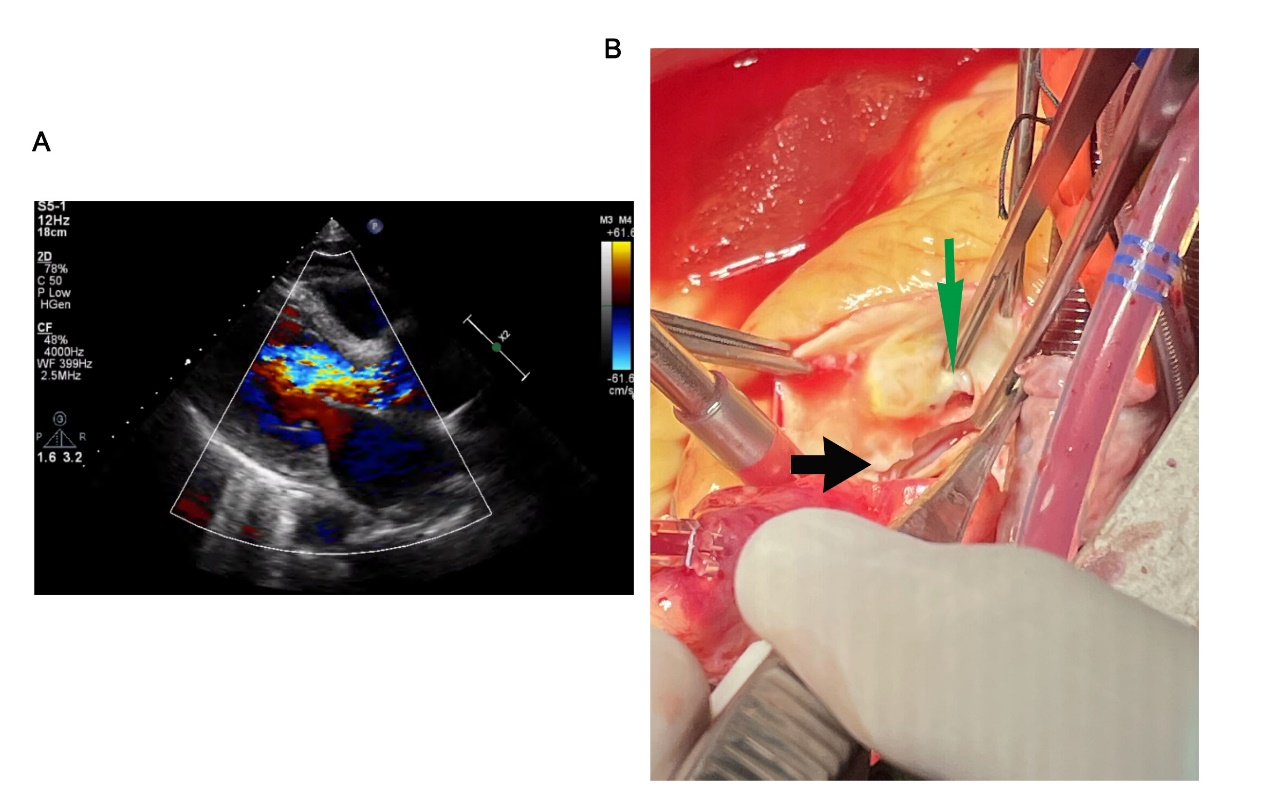

面对这样一个病情复杂危重的患者,周教授带领团队临危不乱,有条不紊的处理了各种突发情况,为患者进行了体外循环支持下开胸手术,开胸后直视下果然验证了MDT专家们一直没有放弃的诊断,右冠状动脉开口下缘有一道约2厘米长的裂口并累及瓣叶,而上翘的内膜片刚好压迫到右冠开口。原来正是这片小小的内膜片压迫了冠脉开口闯下危及生命的天下大祸,也给超声医生挖了个“大坑”误判之为感染性心内膜炎的赘生物形成,周教授当即果断决定切除此“赘生物”并送病理检查及细菌培养。然而更让在场的所有人都想不到的是,周新民做了一个更大胆的决定,他坚定认为患者如此危重情况绝不过可能承受数次大手术的打击,他果断决定将冠脉搭桥、主动脉瓣生物瓣置换和升主动脉置换(Bentall手术)以“一站式”完成。而接下来手术中面对组织脆弱缝针难,创面广泛渗血止血难等多道难关周教授率领的手术团队均从容应对,一一化解,足显艺高者人胆大!而术后心衰、感染、出血等重重困难,也在医院医护团队的精心救治下各个击破,化险为夷。

图3. 外科手术直视可见右冠开口下缘主动脉内膜片撕裂